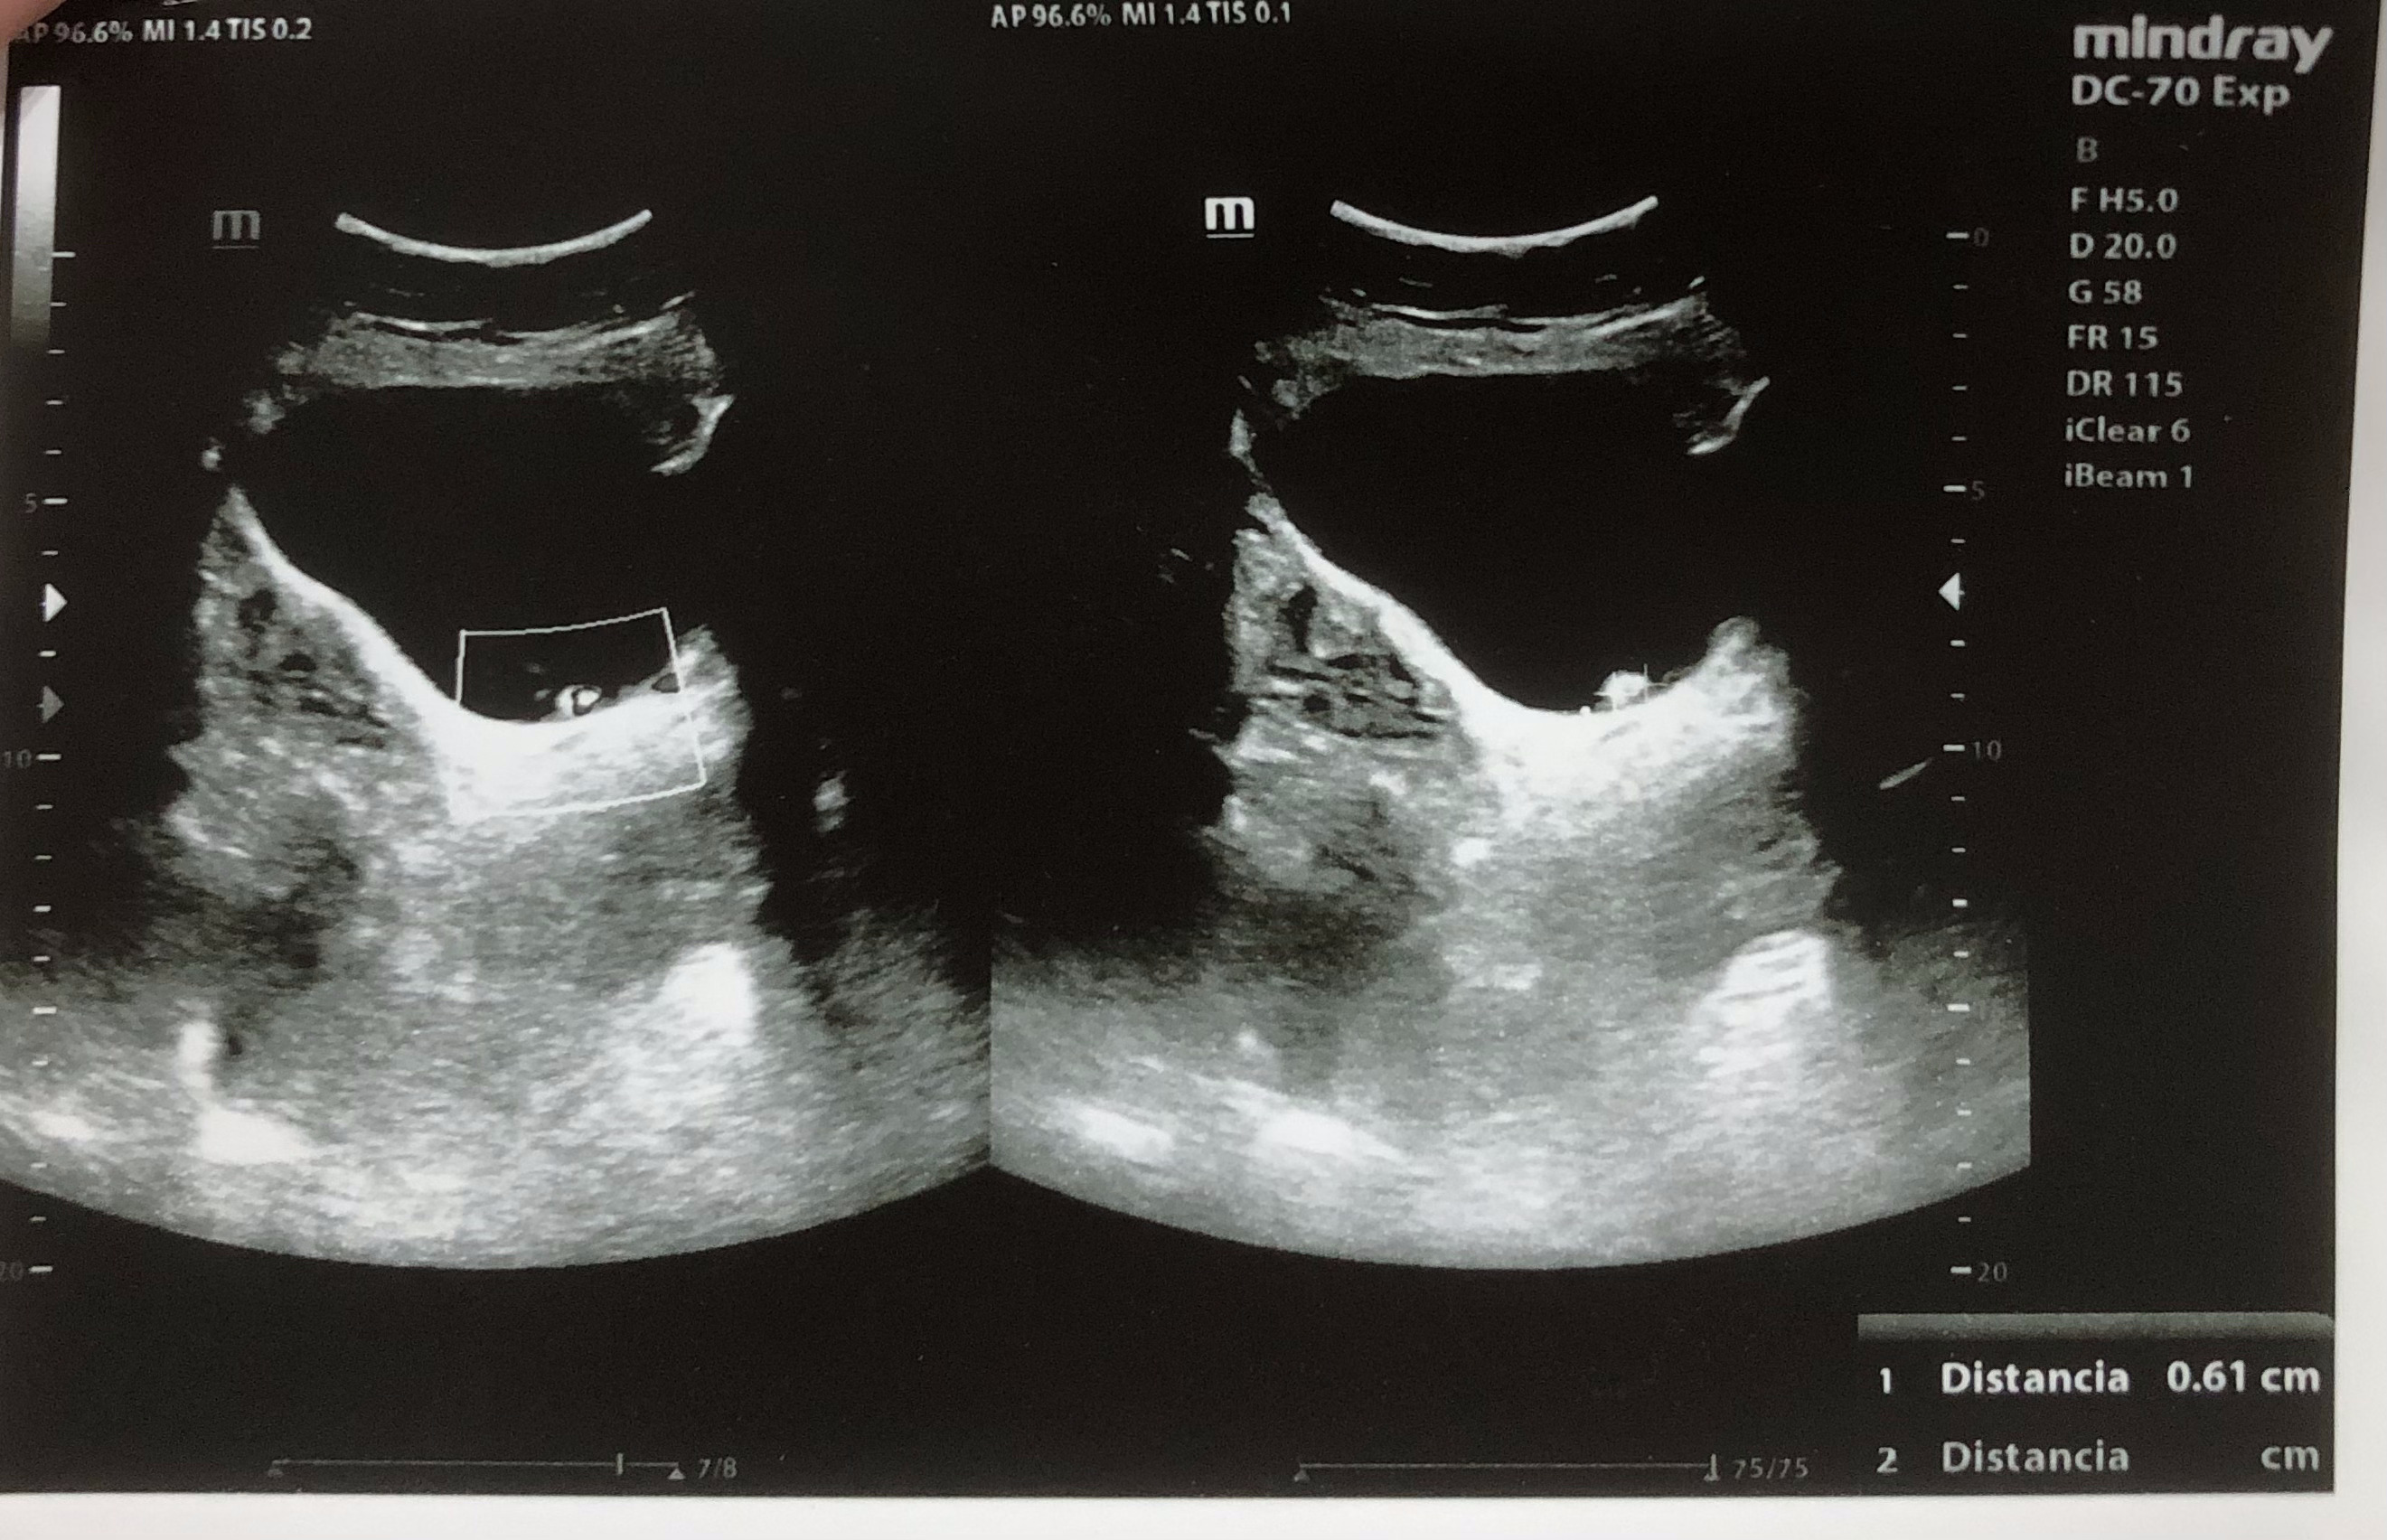

Se realiza ecografía renal donde se aprecia lesión hiperecogénica redondeada en pared inferior derecha de vejiga sin sombra posterior de 0,7 x 0,61 cm, que no se moviliza con cambios posturales de la paciente. Centelleo dudoso.

Litiasis vs lesión de características malignas.

Se realiza citoscopia y deciden resección transureteral con resultado de anatomía patológica de carcinoma urotelial de vejiga.